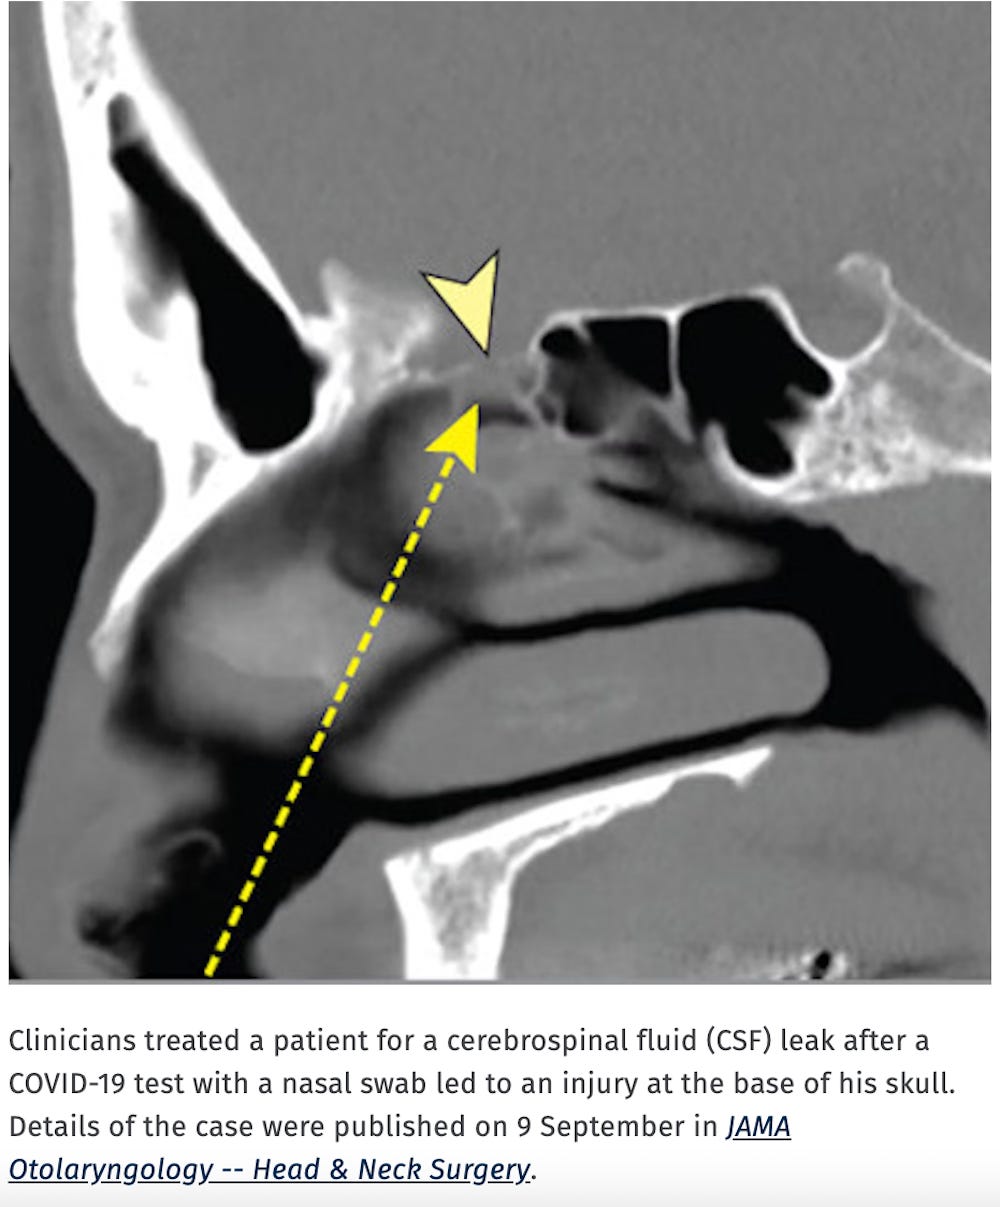

Cribriform Plate Injury After Nasal Swab Testing for COVID-19

An otherwise healthy man in his 40s presented for right-sided clear water rhinorrhea in December of 2020. Rhinorrhea originated after nasal swab testing and was mistakenly considered to be allergic rhinitis in the patient. The test was performed by a mobile unit at the patient’s home in March of 2020. The test was indicated because of previous contact with a woman who had a positive COVID-19 test result 5 days earlier. The patient had no symptoms of COVID-19 infection and RNA of SARS-CoV-2 was not detected by polymerase chain reaction (PCR) testing.

https://jamanetwork.com/journals/jamaotolaryngology/fullarticle/2784128

CT reveals shocking injury caused by COVID-19 nasal swab

The man, who had no previous injury to his skull and was otherwise healthy, underwent COVID-19 testing after being in contact with a woman who had tested positive for SARS-CoV-2. He had no COVID-19 symptoms, and his polymerase chain reaction (PCR) test result was negative.

An analysis of the patient's nasal discharge showed a high level of the beta-trace protein (23.7 mg/L) in the nasal secretion (normal range < 6 mg/L). The beta-trace protein test is a quick, noninvasive, and inexpensive method to detect CSF fluid in nasal secretions.

"Every instance of unilateral clear water rhinorrhea that appears after transnasal testing must be considered a potential CSF leak," the team wrote.